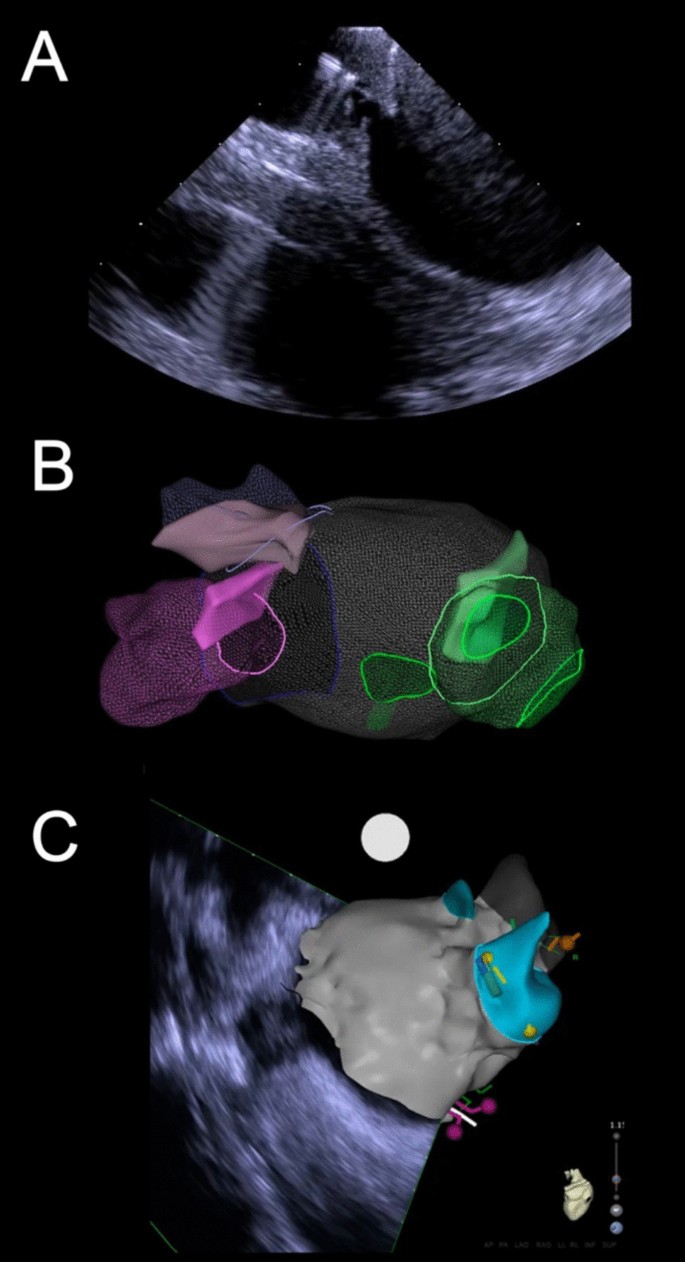

The use of cardiac imaging in patients undergoing atrial fibrillation ablation | Journal of Interventional Cardiac Electrophysiology